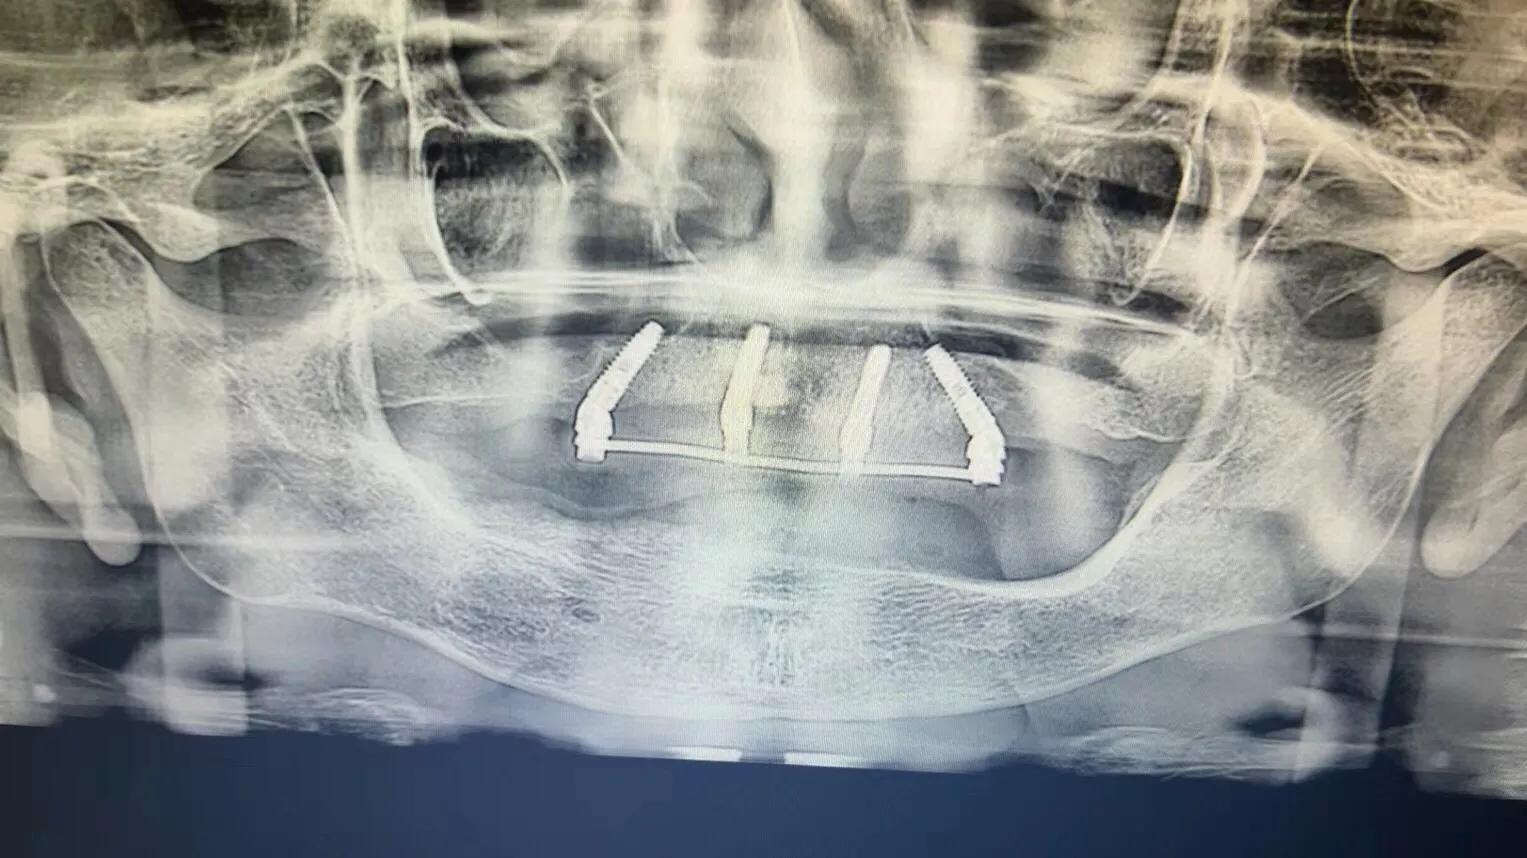

典型的負重,All-On-4。

這就是傳說中的當天戴牙當天吃飯,網(wǎng)上到處宣傳的就是這種種植方法。但是不是每一個人都能做這個,All-on-4一般需要預約,醫(yī)生種植完畢,技師馬上開始取模做牙,大概5小時左右就可以戴上臨時牙回家吃飯了,休息一兩天,正常吃飯是沒問題的。

2. 還有一個問題就是骨件,不是每個人都可以做。骨頭太差,只能做常規(guī)的種植,等3-6個月戴牙,可能更久,中間只能用臨時牙過度。負重開始戴的也是臨時牙,但是這個臨時牙和常規(guī)島臨時牙不一樣,咬合力挺好